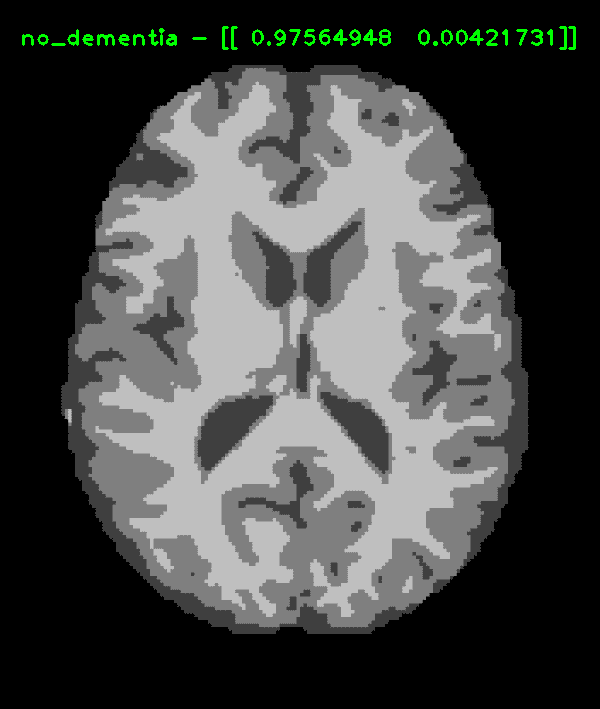

Dementia classifier convolutional neural network built with transfer learning

Cover Image for Dementia classifier convolutional neural network built with transfer learning

Convolutional neural network (CNN) from transfer learning to detect varying levls of dementia in MRI scans.